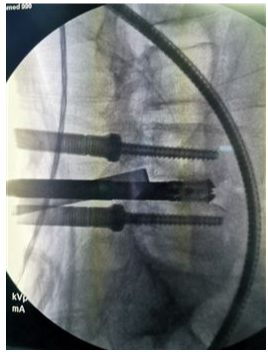

奧蘇本UBE技術(shù)概UBE技術(shù)即單側(cè)雙通道內(nèi)鏡技術(shù)(Unilateral Biportal Endoscopy Technique),適用于頸椎、胸椎、腰椎的退行性病變。與椎間孔鏡的單通道不同,該技術(shù)通常建立兩個(gè)通道,一個(gè)為觀察通道,一個(gè)為器械操作通道。觀察通道一般會(huì)用到0°或30°UBE內(nèi)鏡,操作通道使用UBE專(zhuān)器械,如UBE刮匙、磨鉆(UBE內(nèi)鏡磨頭)、UBE內(nèi)鏡刨刀、UBE內(nèi)鏡消融電極、UBE椎板咬骨鉗、UBE髓核鉗、UBE神經(jīng)拉鉤等。UBE技術(shù)的專(zhuān)用器械包,通過(guò)UBE技術(shù)還可以完成鏡下融合手術(shù)。

該技術(shù)開(kāi)展脊柱手術(shù)時(shí),克服了中心管狹窄、側(cè)管狹窄和椎間孔狹窄的局限。手術(shù)入路角度范圍廣,在不損傷脊柱結(jié)構(gòu)完整性的前提下,有效地對(duì)椎管進(jìn)行了周向和局部減壓,保留了肌肉韌帶附著通過(guò)肌間間隙,保護(hù)背支內(nèi)側(cè)支,從而防止?fàn)繌垞p傷。這種內(nèi)窺鏡入路允許從對(duì)側(cè)后入路和孔外入路(椎旁孔外入路)進(jìn)入孔,為治療所有類(lèi)型的狹窄提供了靈活性,因此,UBE技術(shù)作為一種微創(chuàng)的融合方法,具有極強(qiáng)的實(shí)用性。